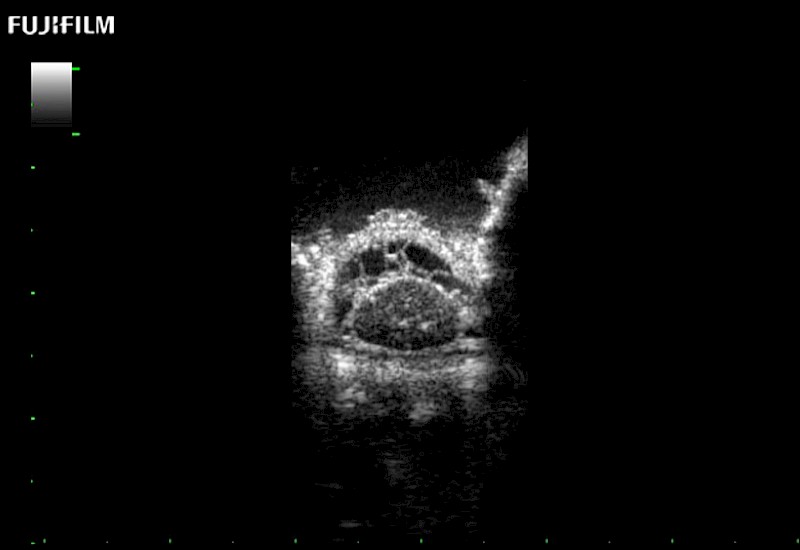

Extraordinary high-resolution digital imaging

for use during: Cranial guidance, Burr-Hole guidance, Spinal Cord guidance, Pituitary guidance, Micro-Surgery guidance